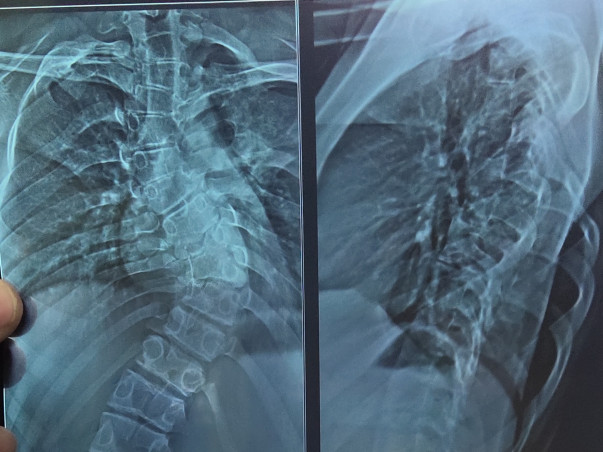

Hello all this is Gowtham from Bangalore on behalf of my cousin sister. Her name is Tejashwini she had problem in back bone, and we were referred with Dr.Shashidar (Bone specialist) in Columbia Asia hospital, DOCTOR told that we have to do surgery of spinal cord it cost around 6.5L to 7L.